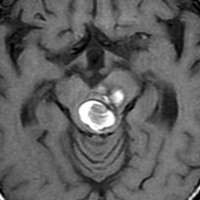

脳槽に増大する海綿状血管腫

このタイプも髄液腔にあるので増大速度が速いです

左聴力低下で発症した小脳の海綿状血管腫で,小脳橋角槽に突出するように増大しています。

左上が発症時,次が1ヶ月後,3ヶ月後,4ヶ月後と急速に大きくなったので摘出しました。

静脈奇形を伴っていませんでした。